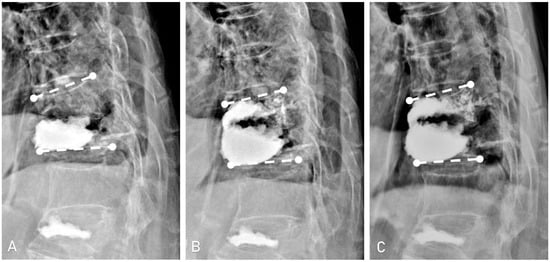

| Kyphotic deformity (°) | |||||

| Single kyphotic angle ‡ | 13.4 ± 9.7 | 8.6 ± 7.0 | 10.3 ± 9.1 | <0.01 | 0.05 |

| Two-segment kyphotic angle § | 15.6 ±11.8 | 12.6 ± 10.0 | 15.2 ± 10.1 | 0.02 | 0.03 |

| Vertebral body height (cm) | |||||

| Anterior vertebral body height | 1.9 ± 0.7 | 2.2 ± 0.6 | 2.3 ± 0.6 | <0.01 | 0.2 |

| Mid vertebral body height | 1.7 ± 0.5 | 1.9 ± 0.5 | 1.9 ± 0.5 | <0.01 | 0.8 |